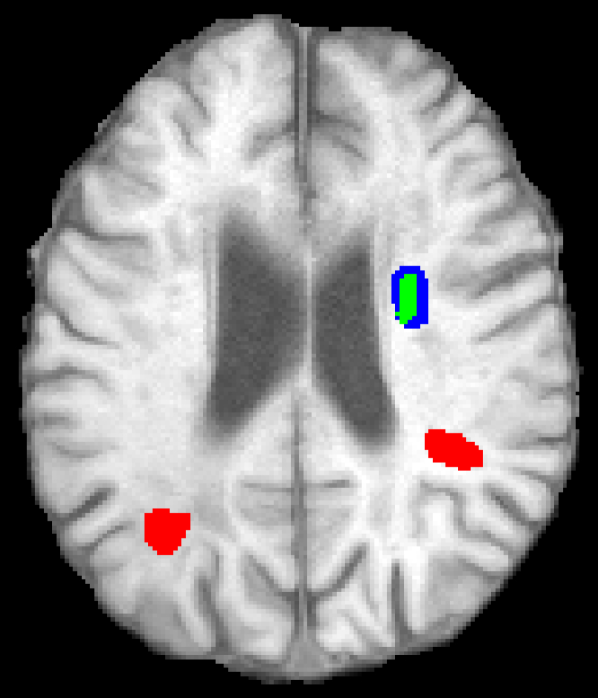

Figure 5 shows qualitative results of four representative segmentation examples from the proposed method. In general, the majority of the lesion is correctly segmented with minor border and small hole inaccuracies as seen in cases 11 and 26. Other less typical errors include under or oversegmentation of the lesion, as seen in case 2 where false positives are found on the upper part of the lesion. In the example of case 15, the lesion is undersegmented due to a confounding unusual appearance of some parts.

Figure 5: Output segmentation masks of representative cases from the training images of ISLES 2015 SPES dataset. On all images, true positives are denoted in green, false positives in red and false negatives in blue.